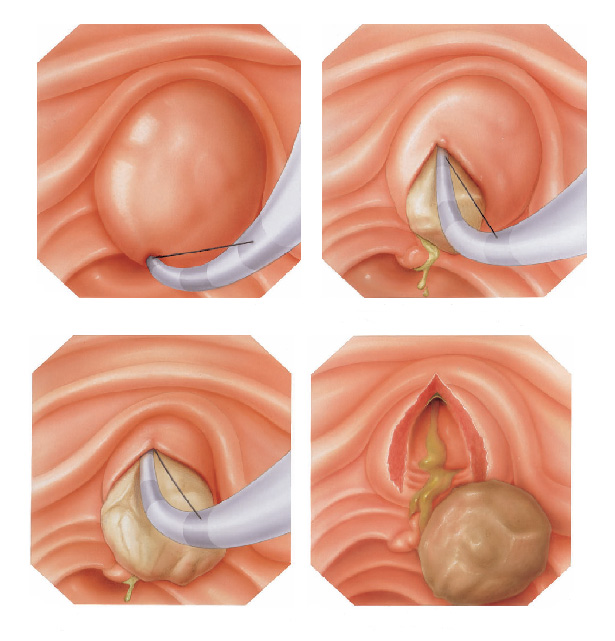

Pacientes que têm o objetivo de emagrecer, podem ter como alternativa a passagem de um balão intragástrico. A passagem do balão é realizada por endoscopia e o procedimento dura cerca de 20 a 30 minutos.

Passagem de Balão Intragástrico

1. O balão intragástrico é introduzido desinsuflado durante a endoscopia e colocado no estômago.

2. Um líquido azul (azul de metileno diluído em soro fisiológico) é colocado dentro do balão através de uma válvula. O volume varia entre 500-700 ml.

3. O aparelho de endoscopia é removido e o balão intragástrico pode ser deixado por um período de até 6 meses.

Pacientes que têm o objetivo de emagrecer, podem ter como alternativa a passagem de um balão intragástrico. A passagem do balão é realizada por endoscopia e o procedimento dura cerca de 20 a 30 minutos.

Passagem de Balão Intragástrico

1. O balão intragástrico é introduzido desinsuflado durante a endoscopia e colocado no estômago.

2. Um líquido azul (azul de metileno diluído em soro fisiológico) é colocado dentro do balão através de uma válvula. O volume varia entre 500-700 ml.

3. O aparelho de endoscopia é removido e o balão intragástrico pode ser deixado por um período de até 6 meses.